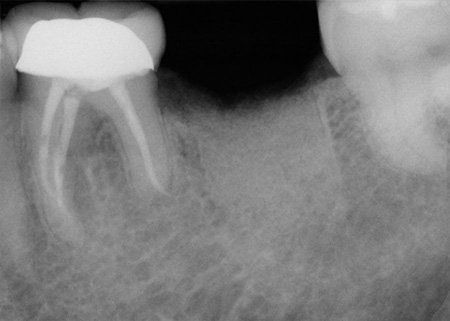

Cracked Tooth

A cracked tooth describes a vertical crack that travels from the surface of the tooth to below the gum line. Because a crack of this kind can affect the pulp of the tooth and lead to infection, the tooth may need to be extracted (removed).